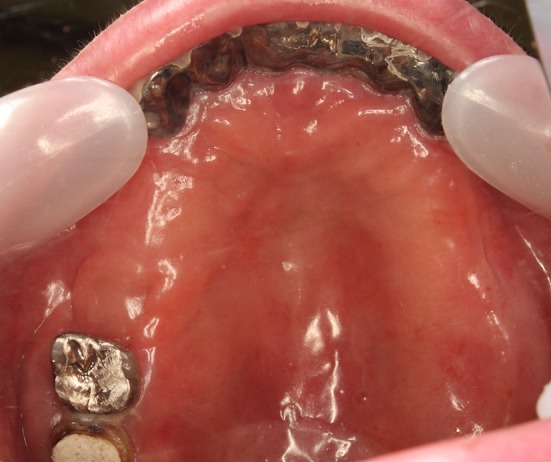

Fig. 10.

Two months after the closure operation. The mucoperiosteal flap was completely engrafted. We confirmed the complete epithelization of the donor part